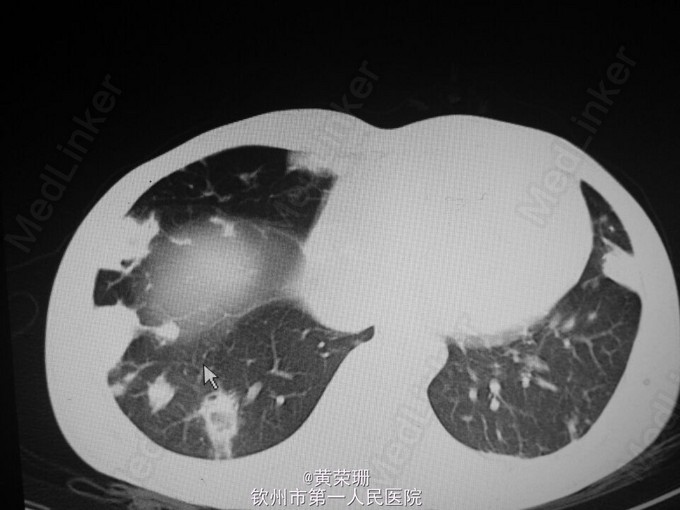

21岁青年男性患者, 急性起病,既往有静脉注射毒品史1月余。因“反复畏寒、发热20余天”入院。自诉20余天前以白开水化“毒品”静脉注射后出现畏寒、发热,体温最高达39.5℃,伴头部胀痛,浑身乏力,伴气促,活动后明显,伴咳嗽、咳痰,间中伴暗红色血丝痰,伴呕吐,为胃内容物,无明显腹痛、腹胀等。于当地门诊予“退热针”治疗后可退热,但易反复,15天出现双下肢几颜面部浮肿,于当地医院住院治疗,检查提示:WBC 25.4*10^9/L,Hb 58.2g/L,痰培养提示:金黄色葡萄球菌,伴少量白色念珠菌伴随生长。心脏B超:三尖瓣脱垂并关闭不全,治疗上余抗感染、输血、利尿等对症处理,但仍间中发热,遂至我院。 入院查体:心率112次/分,贫血貌,两肺呼吸音粗,双肺可闻及湿啰音,心界不大,心率112次/分,率齐,心音有力,三尖瓣听诊区可闻及3/6级收缩期吹风样杂音。 辅助检查:心脏B超:1.三尖瓣前叶赘生物(感染性心内膜炎),伴瓣口反流(重度)及前瓣穿孔,右房增大;2.左心室收缩功能测量值正常范围(图1)。胸部CT:1.考虑两肺感染(真菌感染?细菌感染?),2.两侧胸膜轻度增厚(图2-4)。入院后反复血培养、痰培养均未见培养出细菌几真菌。 主要诊断:1.感染性心内膜炎 三尖瓣赘生物并穿孔 三尖瓣重度关闭不全 2.肺部感染 患者入院后“哌拉西林他唑巴坦+阿米卡星”抗感染、强心、利尿、营养心肌等处理病情平稳后行三尖瓣置换术。术后病理:(三尖瓣)镜下见纤维性瓣膜局部增厚伴大量急慢性炎性细胞浸润,可见小脓肿形成,切表面有红染纤维素样炎性渗出物附着,结合临床符合感染性心内膜炎改变(图5)。